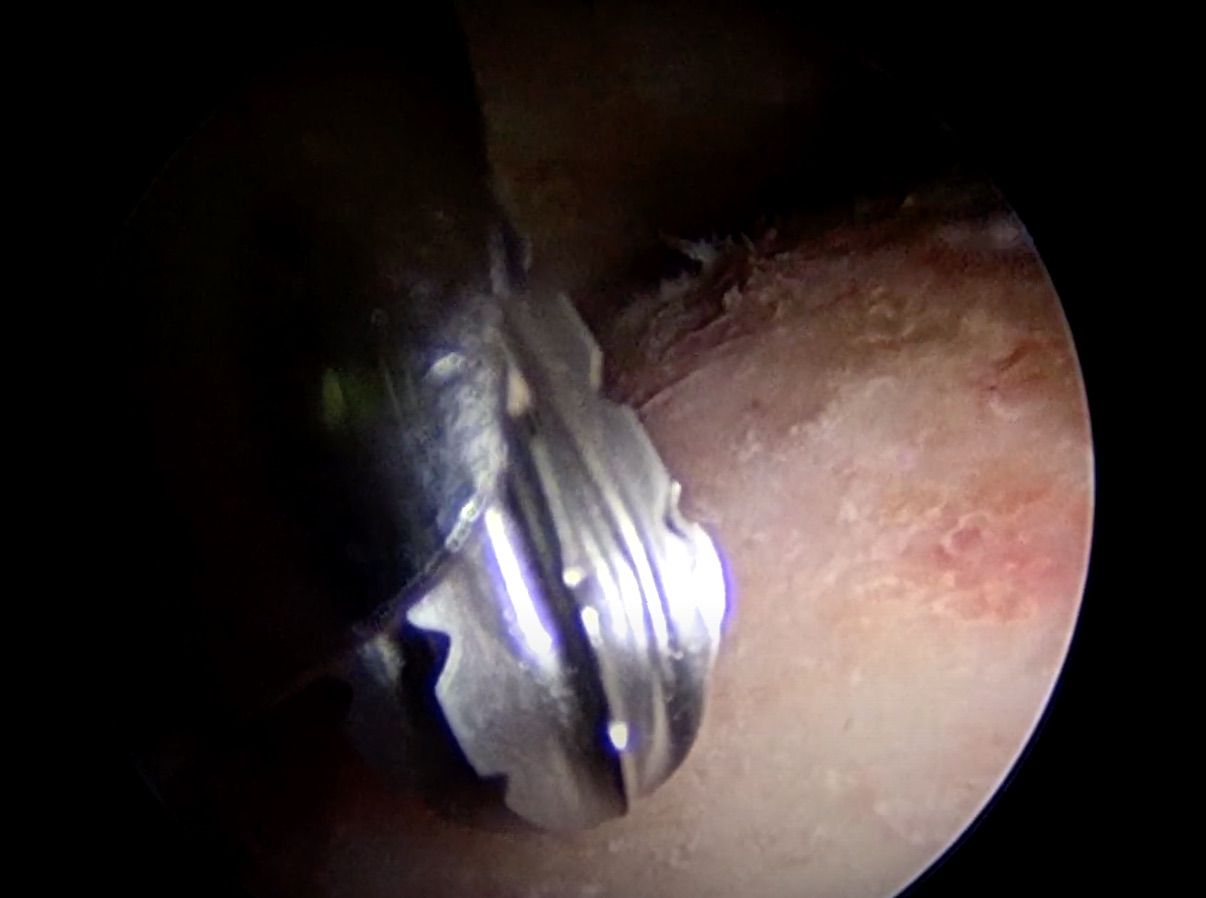

The MRI was in July and it was immediately apparent I had a cam impingement in my left hip. Well crap.

Bonus content: If you've ever wanted to see the inside of my hip, you're in luck. Warning: It's nasty.